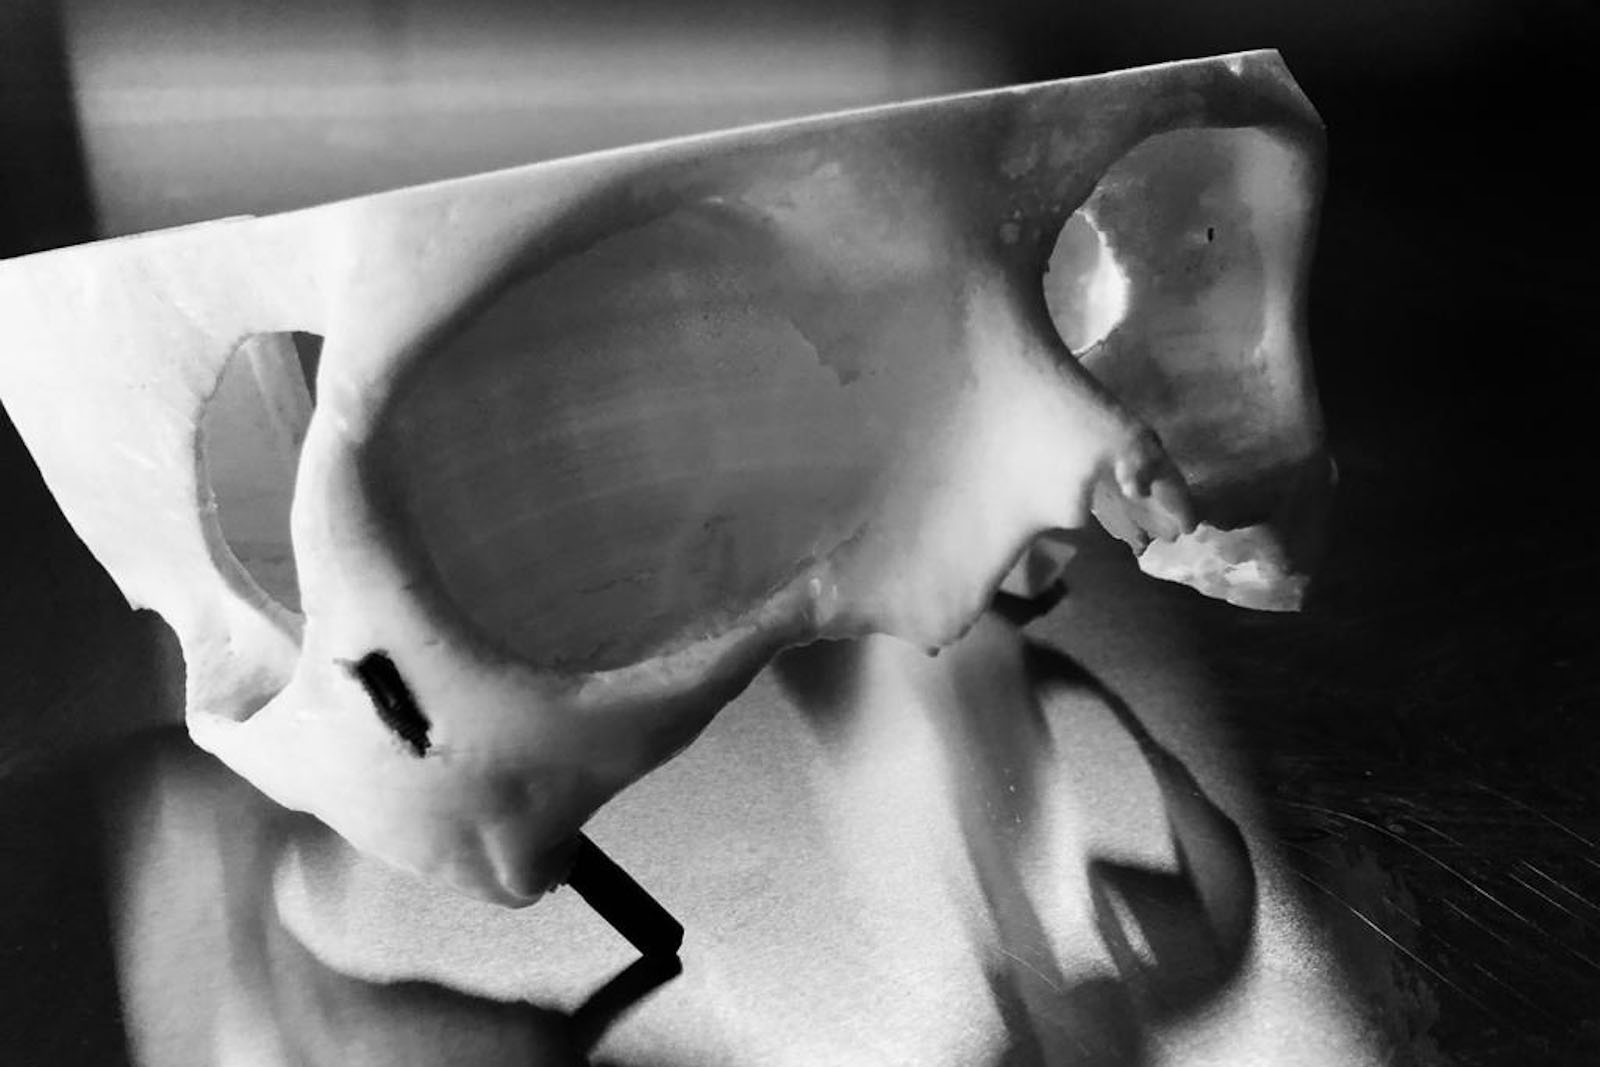

Chory po resekcji tkanek/narządów twarzoczaszki wymaga wnikliwej diagnostyki obrazującej zakres ubytku oraz stan podłoża kostnego. Wykonuje się zdjęcia radiologiczne RTG pantomograficzne szczęk OPG, konwencjonalną tomografię komputerową CT, stożkową tomografię komputerową CBCT, ukazującą trójwymiarowy obraz twarzoczaszki, oraz w razie potrzeby rezonans magnetyczny NMR. Możliwy jest również druk modeli 3D w skali 1:1 dowolnej części twarzoczaszki.

Diagnostyka ma za zadanie wykluczenie wznowy wyciętego nowotworu oraz pomoc w ocenie tkanki kostnej w okolicy ubytku. Ocena kości pozwala na zaplanowanie zabiegu wszczepienia implantów jako przyszłego fundamentu niezbędnego dla mocowania protez poresekcyjnych lub epitez twarzy.

Zastosowanie współczesnych technik obrazowania trójwymiarowego umożliwia precyzyjne zaplanowanie pozycji implantów czaszkowych, tak by ektoprotezę stabilnie osadzić na podłożu.